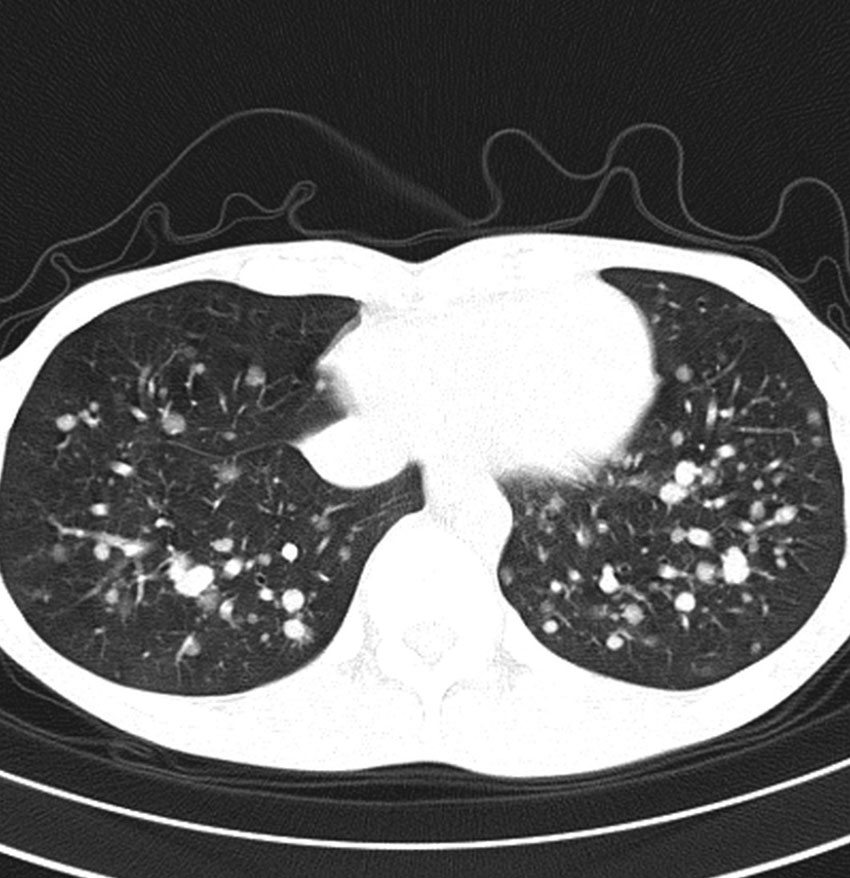

- でもきわめてまれに,頸静脈を介して肺転移します

- 髄膜腫の肺転移と同じような,ゆっくりとした進行という予後となります

- これは頸静脈を介してのこぼれ落ちるような肺転移です

- ですから,頸静脈を遮断するような腫瘍摘出手術をすれば予防できるという考え方もあります

多発性肺転移が発見され無治療で14年が経過しました。肺転移巣は無数ですがたいして増大しませんので普通の生活ができています。